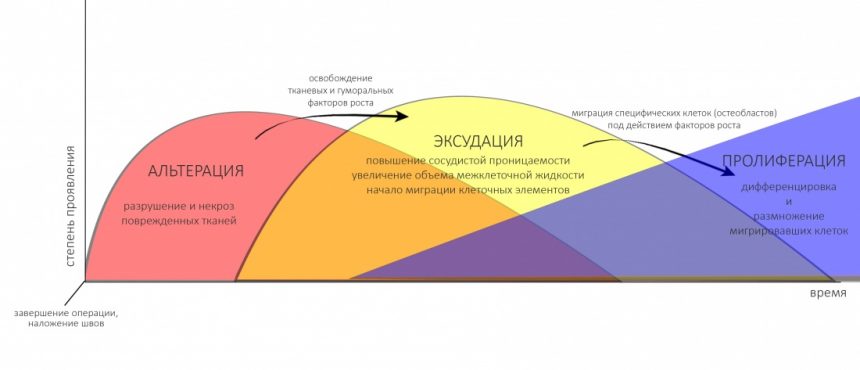

Если мы представим сильно упрощенную динамику послеоперационного воспалительного процесса в виде графика, где по оси абсцисс у нас будет время, а по оси ординат — степень проявления, то получим следующее:

Еще раз повторюсь — динамика на графике представлена очень-очень приблизительно, без учёта фактора инфицирования, влияния ферментов полости рта и общего состояния организма. Однако, она наглядно объясняет симптоматику (появление болей, отеков, кровотечений и т. д.) послеоперационного периода и то, почему после хирургического вмешательства нужно принимать определенные лекарства и соблюдать рекомендации врача.

Пролиферация, последняя фаза послеоперационного воспалительного процесса, характеризуется усилением деления клеток и, как следствие, регенерацией поврежденных тканей. Если мы говорим именно о костной ткани челюстей, то на клеточном уровне это происходит следующим образом: